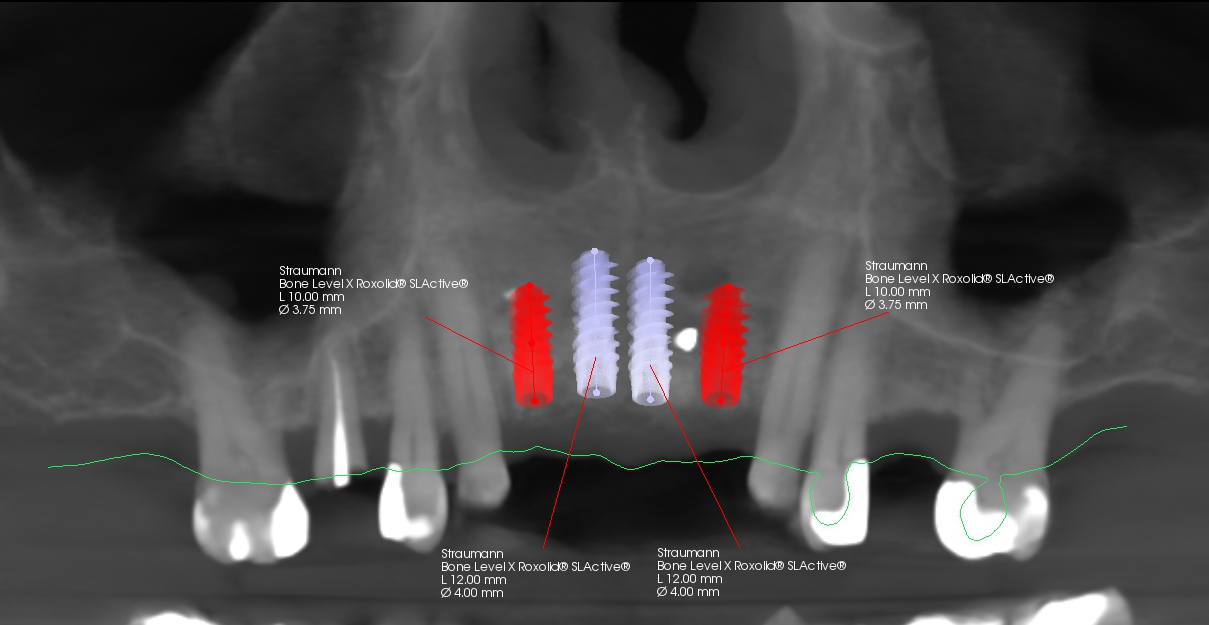

Fig. 9: Implant planning for all four positions.

During the implant planning phase, we created a preliminary plan using 3D imaging software with a prosthetically driven implant planning approach (Figs. 9 & 10), and the plan was exported into surgical guide planning software for final planning and construction of the surgical drilling guide (Figs. 11a–c). The implants were planned in all four positions with the object of identifying the two most optimal and accessible sites for the placement of two implants and the corresponding bridge restoration.

Fig. 10: Final planning for two implants with merged intra-oral scan and CBCT data.